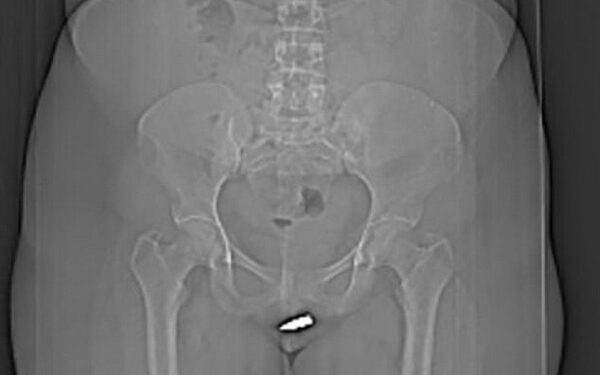

Un scanner a été pratiqué et a révélé que le projectile s’était logé à l’intérieur de son clitoris.

Selon les premiers éléments de l’enquête, la balle, de 2 cm de long et de 0,8 cm de diamètre, aurait traversé le plafond avant de venir se planter dans l’organe génital de la victime.